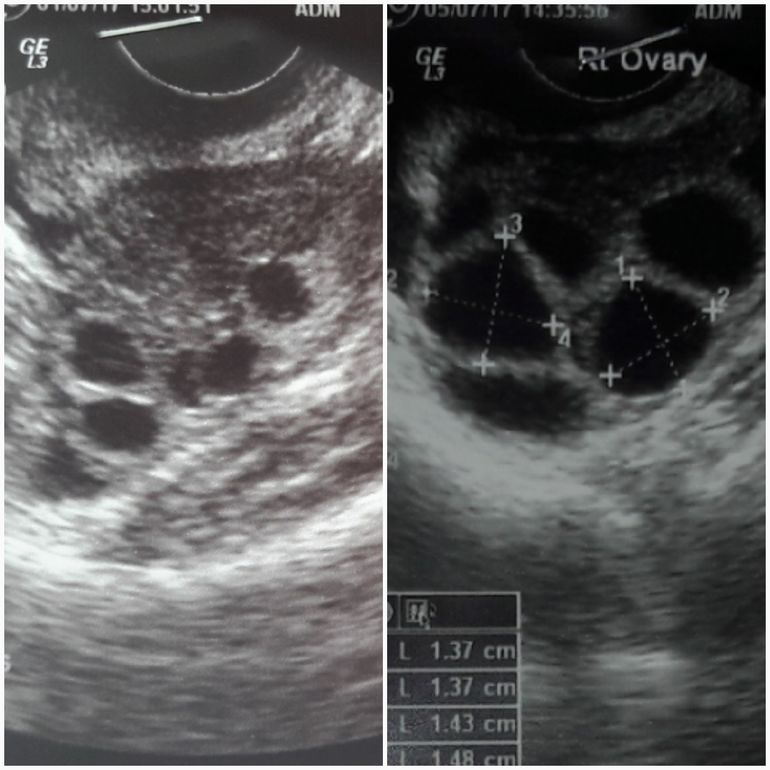

Была на я втором УЗИ у своего Ре, фолликулы растут, но только в правом яичнике, эндометрий хороший...Так как фолликулов не много, решили делать ЭКО с ИКСИ.

Контрольное УЗИ в субботу, а на понедельник 10.07 назначили пункцию...страшновато что то...

Из лекарств подредактировали дозировку... Мерионал75+Альтерпур75 и добавили Оргалутран 0,25...